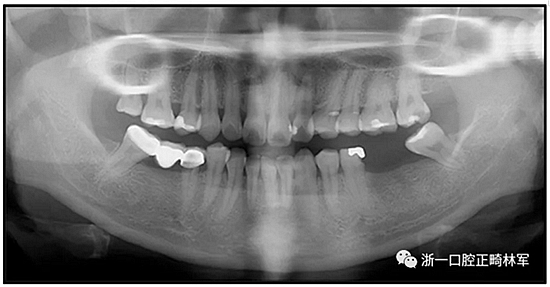

36歲;女性;尋求下頜左后方區(qū)域間隙管理的建議(圖1和圖2),通過(guò)治療獲得了良好的牙頜面效果(圖3和圖4)。她被診斷患有骨性I類(lèi)和代償性牙性II類(lèi)錯(cuò)合畸形,并且上頜左側(cè)尖牙缺失(圖1和2)。大約七年前,由于不可修復(fù)的齲齒,拔除了下頜左側(cè)第一和第二磨牙(圖5)。37相鄰的第三磨牙向近中移動(dòng)并傾斜入間隙,導(dǎo)致無(wú)牙頜間隙減小至約14 mm(圖2和圖5)。臨床和影像學(xué)評(píng)估顯示多發(fā)性齲損和在下頜右側(cè)567處有一不良的固定橋修復(fù)體(圖1和5)。此外,下頜左中切牙缺失,造成下頜中線(xiàn)向左側(cè)偏移約3 mm(圖1和圖2)?;颊咦栽V,她的右上第一前磨牙和左上尖牙在13歲時(shí)由其家庭牙醫(yī)拔除,因?yàn)樗鼈儽蛔枞筋a側(cè)萌出(圖1)。上頜第二磨牙缺失(未知病因),并且相鄰的第三磨牙已經(jīng)轉(zhuǎn)移到第二磨牙間隙中。如補(bǔ)充材料所示,美國(guó)正畸學(xué)差異指數(shù)DI是28分。種植體部位(下頜左側(cè)和右側(cè)第一磨牙)由于復(fù)雜性得到額外4分(補(bǔ)充材料)。

總之,這種復(fù)合錯(cuò)合畸形是一個(gè)很?chē)?yán)重的問(wèn)題,需要進(jìn)行認(rèn)真的多學(xué)科序列治療。治療后X光片(圖6)和重疊頭影測(cè)量圖(圖7)記錄了跨學(xué)科治療結(jié)果。

圖5. 治療前的側(cè)位片(上圖)和全景(下圖)的X光片